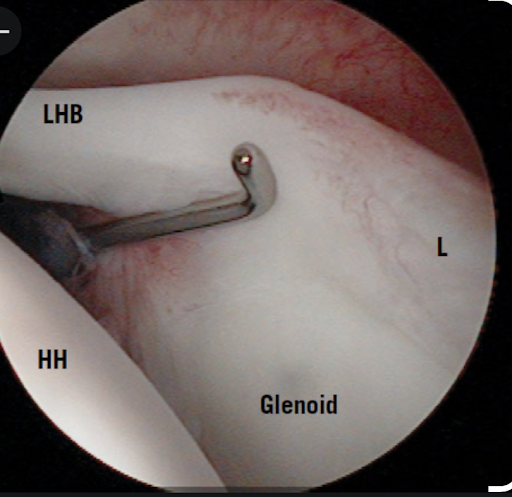

The humerus is secured on the rail by the biceps sheath and the transverse humeral ligament as shown in this arthroscopic view

The biceps sheath and the transverse humeral ligament keep the humerus riding along the rail of the biceps tendon - the stabilizing effect of which becomes greater as the shoulder is elevated, bringing the transverse humeral ligament closer to the supraglenoid tubercle.